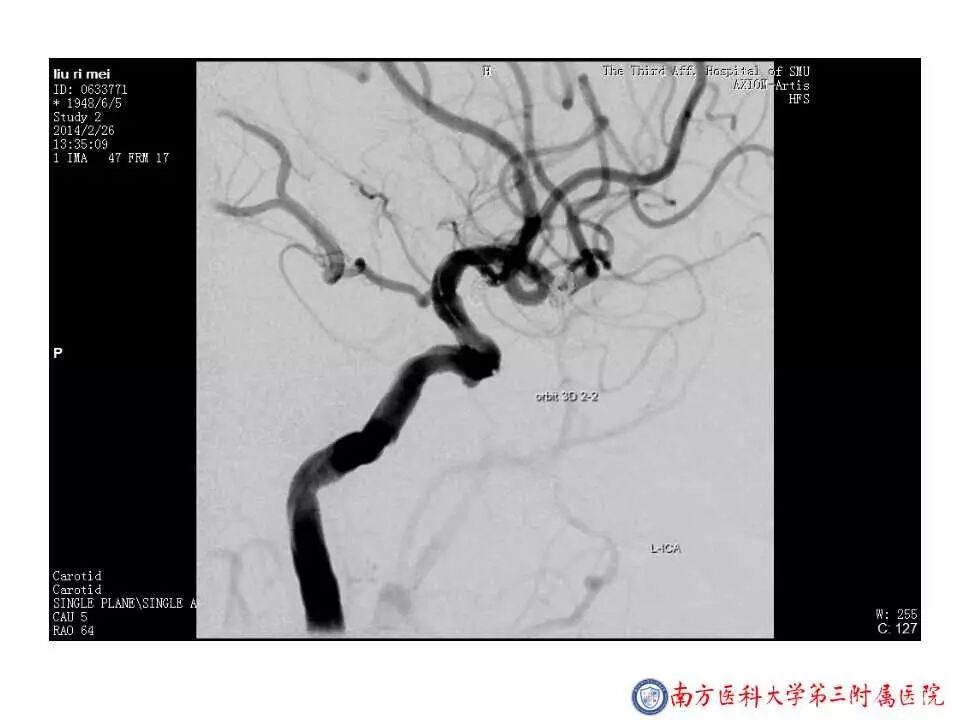

今天为大家分享的是“强生医疗CNV-神经介入专栏”第二十五期,由南方医科大学第三附属医院神经外科主任黄理金教授带来的“Enterprise支架辅助栓塞动脉瘤的优势”精彩讲课视频及PPT,欢迎观看。文章仅代表作者个人观点,如有不同见解,欢迎同道斧正!